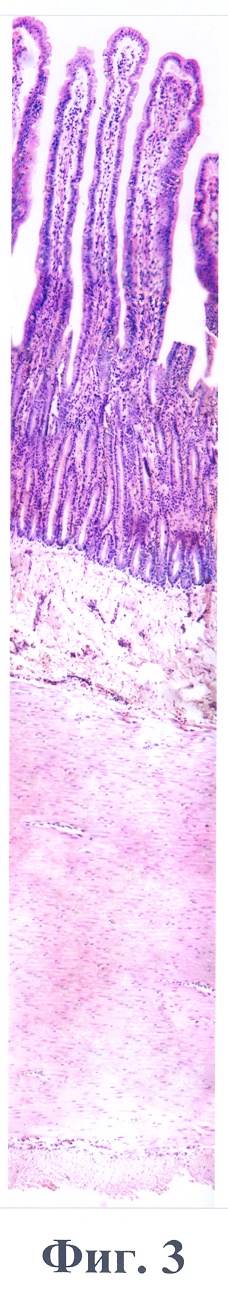

Данный пример иллюстрирует фиг.3, где представлена гистоструктура стенки тонкой кишки кошки №4 через 2 часа после наложения лигатуры на участок кишечника в сочетании с введением серотонина-адипината. Окраска гематоксилин и эозин. Объектив х10. Определяется слабовыраженный отек слизистой и подслизистой оболочек, в области крипт – полнокровные капилляры без кровоизлияний в окружающие сосуды ткани, в мышечной оболочке между циркулярным и продольным слоями единичные полнокровные сосуды с краевым стоянием нейтрофильных лейкоцитов без выхода их за пределы сосудистой стенки. Деструктивных изменений не найдено.